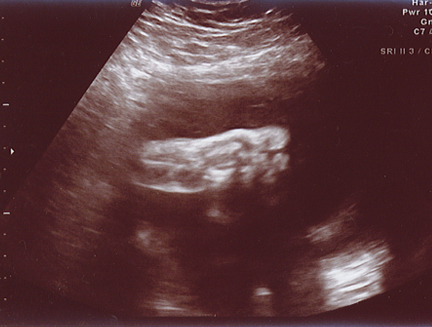

January 20, 2006 - One of the last few ultrasounds...Evan's left foot! He sure is kickin it up. We are still expecting him soon... a few weeks left!!